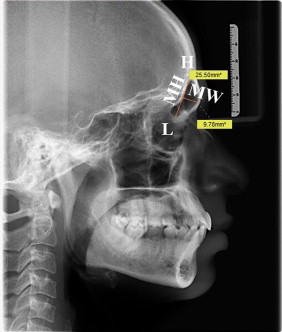

전두동 이라는 곳을 세로로 찍은 사진인데요. 이렇게 세로로 찍더라도 전두동의 모든 부분이 나오는 것인가요? 아니면 일부는 잘려서 나오는 것인가요?

해당 엑스레이는 모든 부비동이 다 포함되는 사진입니다. 다만 겹쳐지는 부분에 대한 평가를 해야하므로 부비동의 평가가 필요하다면 보토 단독으로 촬영하지는 않는 사진이 되겠습니다.